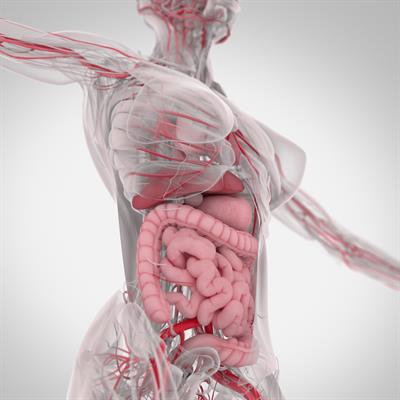

Challenges in the Contemporary Assessment of Coronary Physiology

- Dejan Orlic

- Milorad Tesic

- 16,269 views

- 6 articles